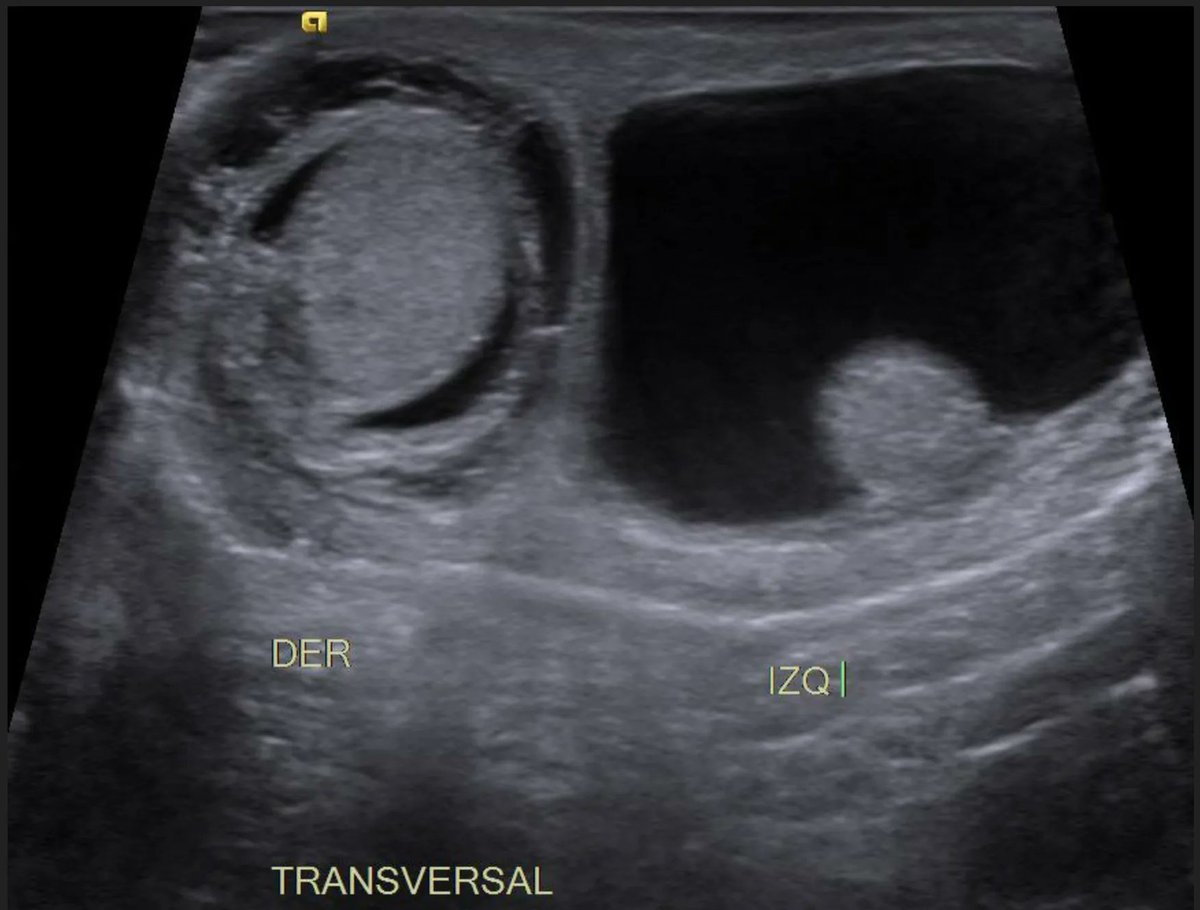

Neonatal testicular torsion. A, Transverse grayscale sonogram of the Testicular Torsion Newborn A testicular torsion occurs when your spermatic cord twists, cutting off blood supply to your testicle. testicular torsion can occur in both newborns and adolescents. testicular torsion in a baby happens when the sac around the testicles doesn’t attach to the scrotum. rotation of the testis around the axis of the spermatic cord results in tissue ischaemia. Testicular Torsion Newborn.